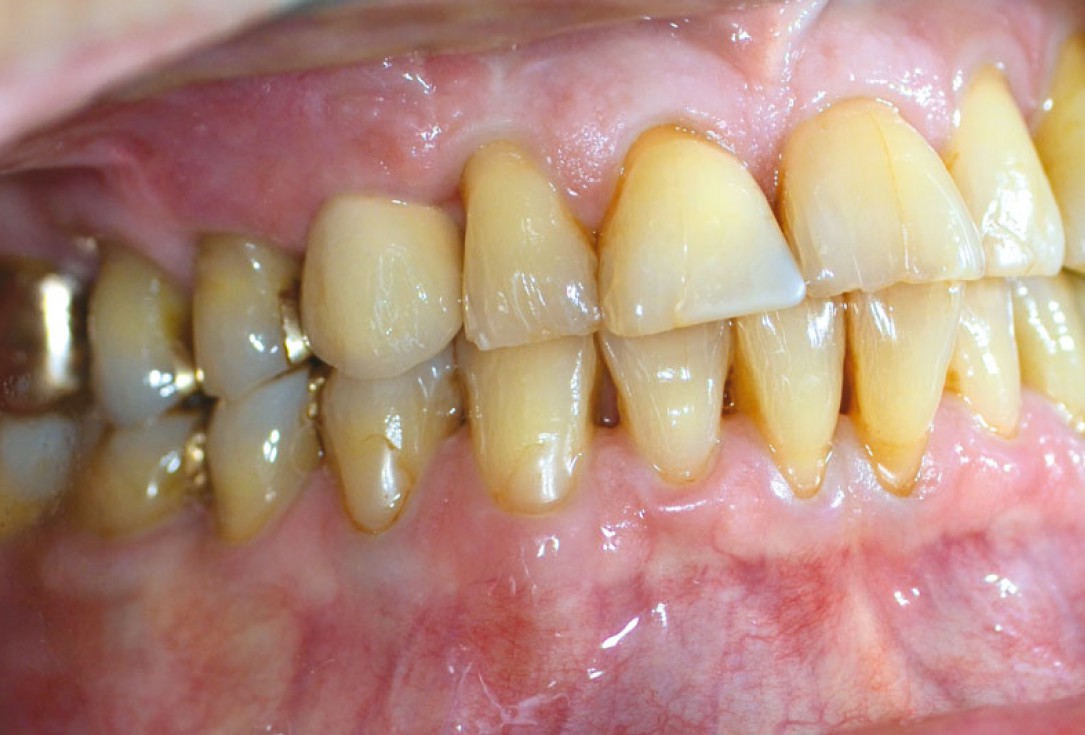

01/12 - Initial situation - bone defect in maxilla after loosing right canine

Block augmentation with maxgraft® in the maxilla - PD Dr. Dr. F. Kloss